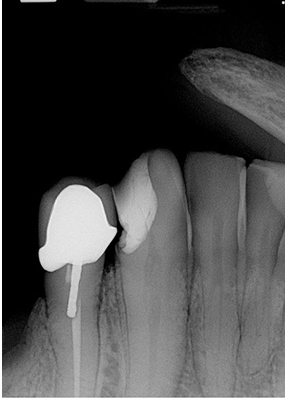

What is the problem with this Wired Cable Issues X-ray?

May occur with direct digital sensors

How would you resolve this Wired Cable Issues X-ray?

Always ensure the cable is not placed between the sensor and source of radiation